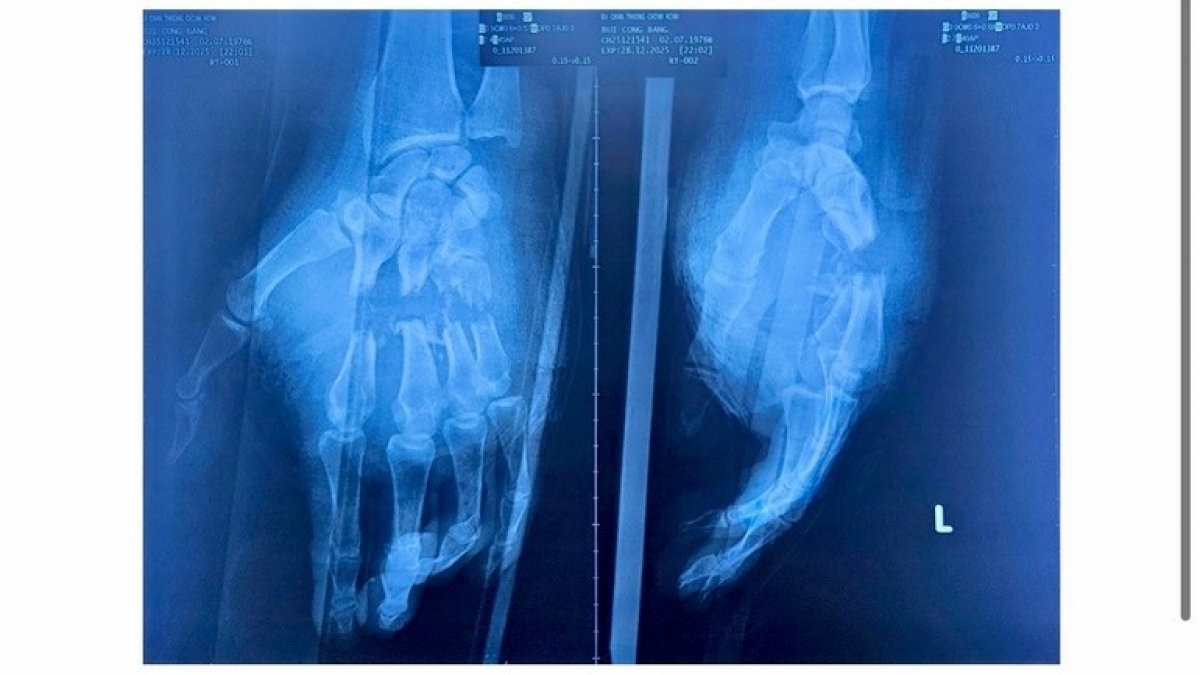

# Mới đây, các bác sĩ Bệnh viện Chấn thương Chỉnh hình TPHCM đã phẫu thuật thành công, cứu sống và bảo tồn chức năng cho bàn tay trái của một nam công nhân bị máy cưa gỗ cắt gây đứt gần lìa nhiều ngón tay – một tai nạn lao động đặc biệt nghiêm trọng. Trước đó, bệnh nhân nam sinh năm 1976, ngụ xã Cửa Cạn, Đặc khu Phú Quốc, tỉnh An Giang, trong lúc đang làm việc thì bất ngờ bị máy cưa gỗ cắt vào bàn tay trái. Tai nạn khiến các ngón II, III, IV và V bị đứt gần lìa. Tại bệnh viện, các bác sĩ cho biết, sau mổ, các ngón II, III, IV, V bàn tay trái của bệnh nhân hồng ấm trở lại, đo được SpO₂, có thể cử động gấp – duỗi nhẹ. Vết thương khô, không có dấu hiệu nhiễm trùng. Đây là kết quả rất khả quan đối với một trường hợp đứt gần lìa nhiều ngón tay, được phẫu thuật trong "giờ vàng" cuối cùng.